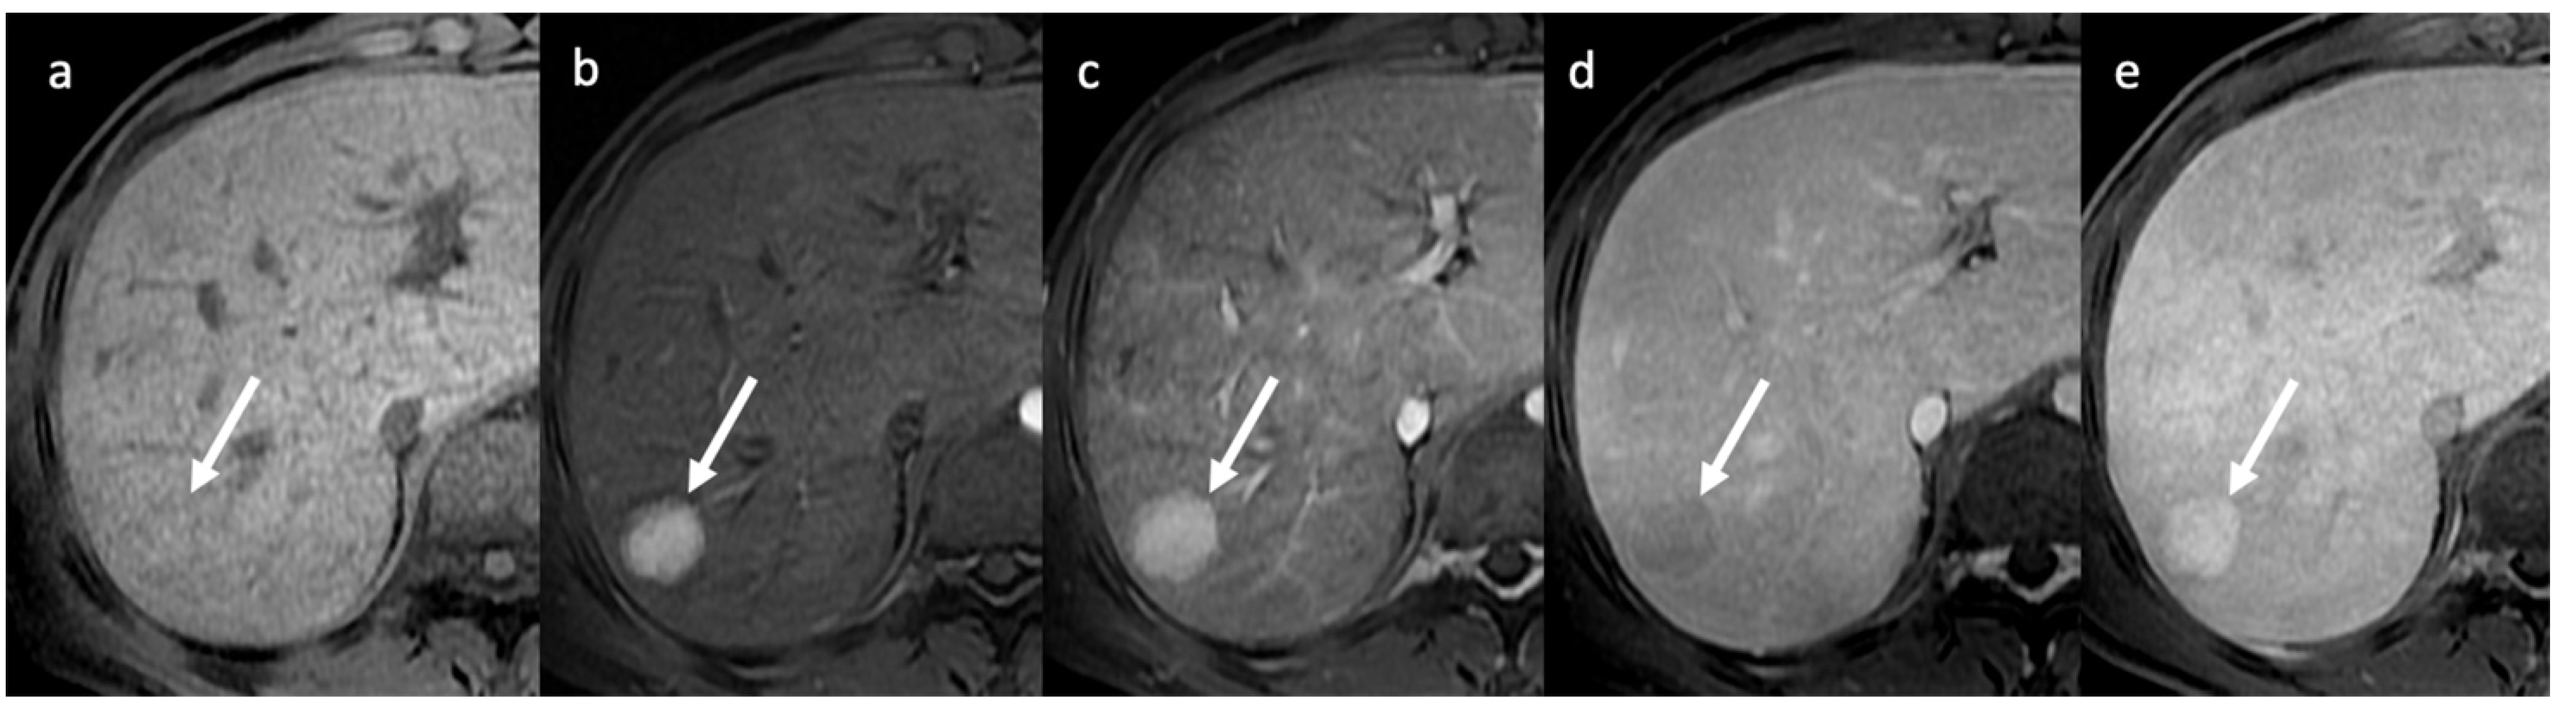

- Indirect signs: non-specific. They represent the consequences of long-standing hepatic venous impairment, including liver parenchymal changes with fibrosis and atrophy of involved segments and hypertrophy of unaffected territories (e.g., caudate lobe hypertrophy). On CT and MRI, centrilobular or sinusoidal congestion, represented as heterogeneous ”mosaic” enhancement after contrast media is also characteristic. Other signs include ascites, portal hypertension, and the presence of benign regenerative nodules, as well as hepatocellular carcinoma [6].

| MRI | Characterization of nodules (FNH-like nodules vs. HCC) T1-w decreased signal in hypoperfused regions, corresponding to high T2-w SI T2*-w flow void corresponding to thrombus. Hypointensity along the occluded vessels |